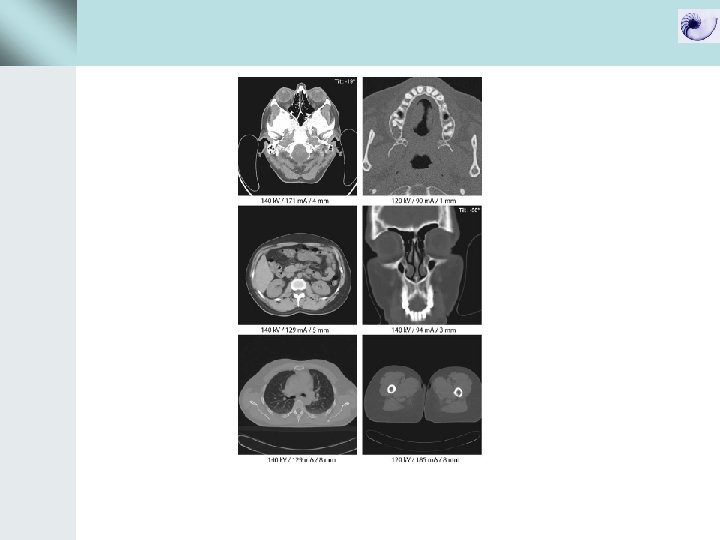

Data acquisition με συμβατικό CT και spiral CT